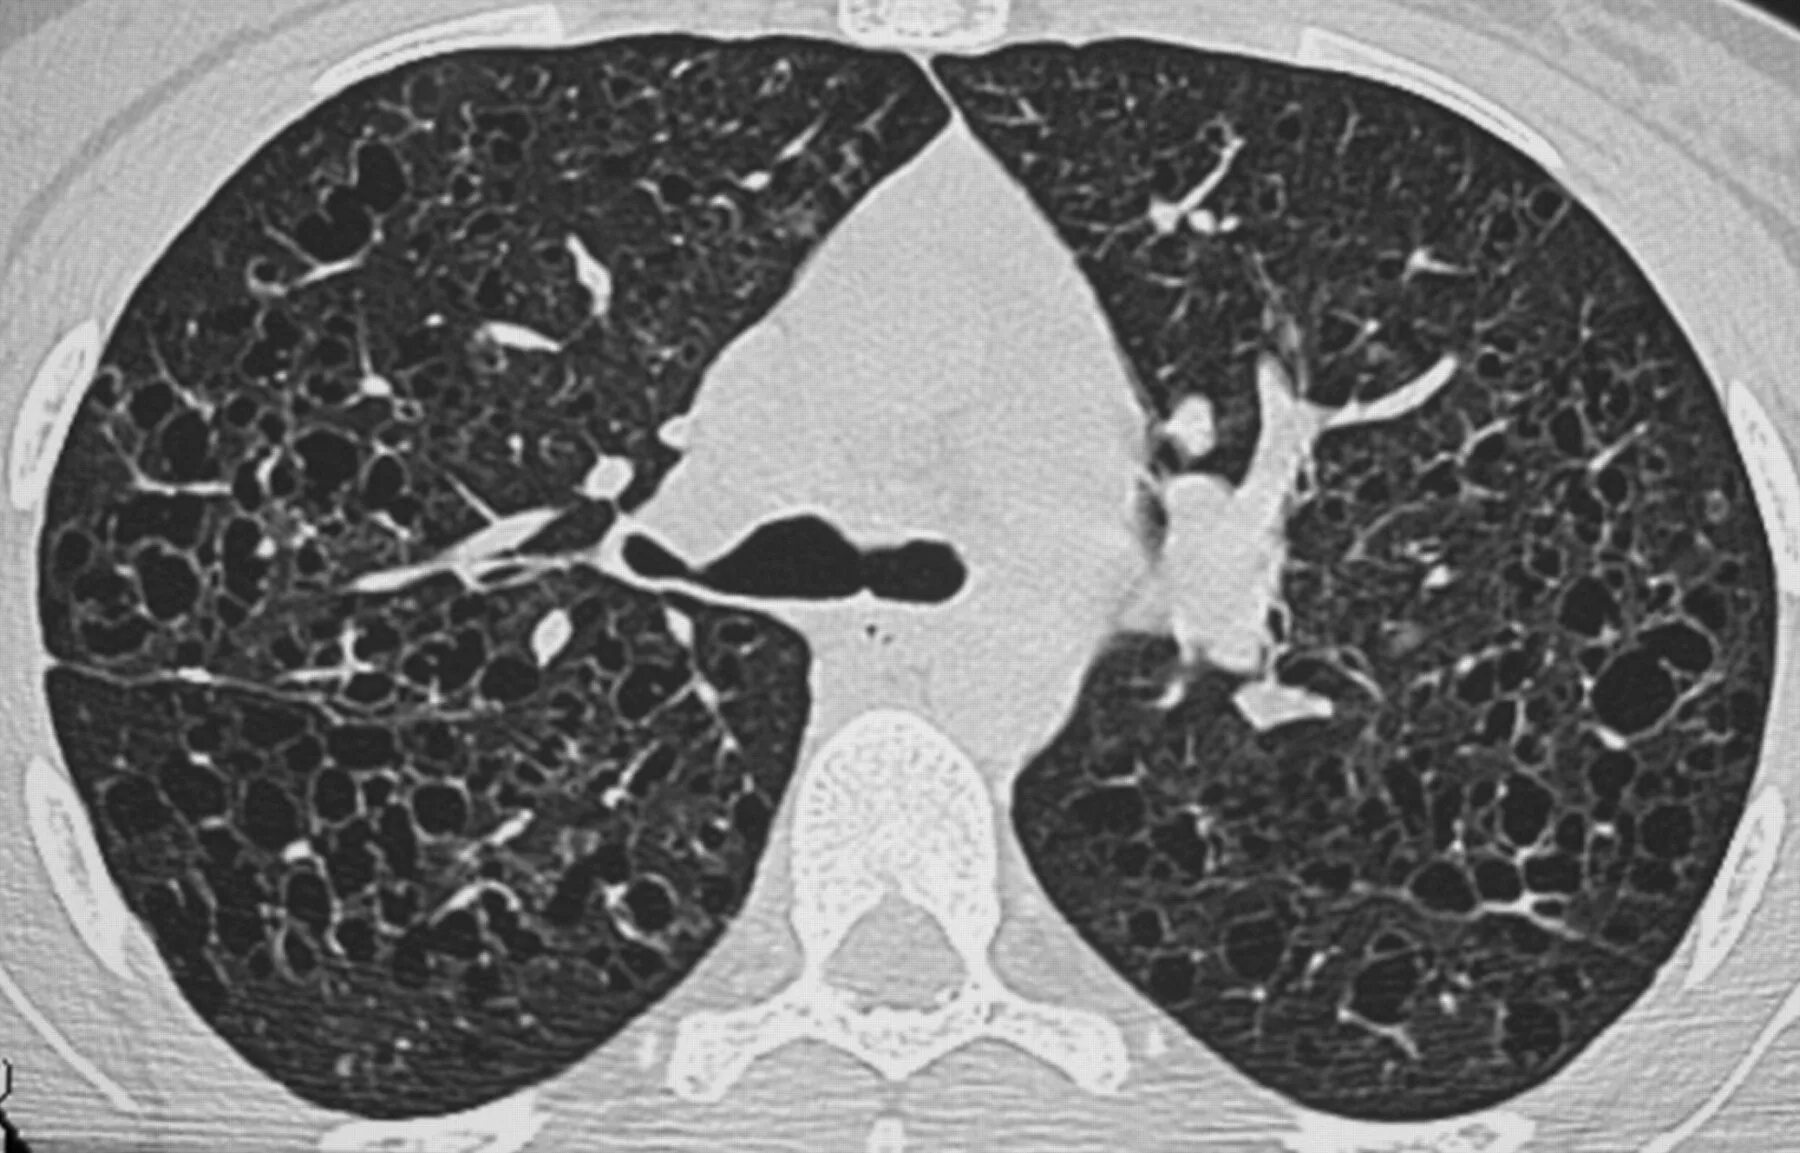

Фиброз кт